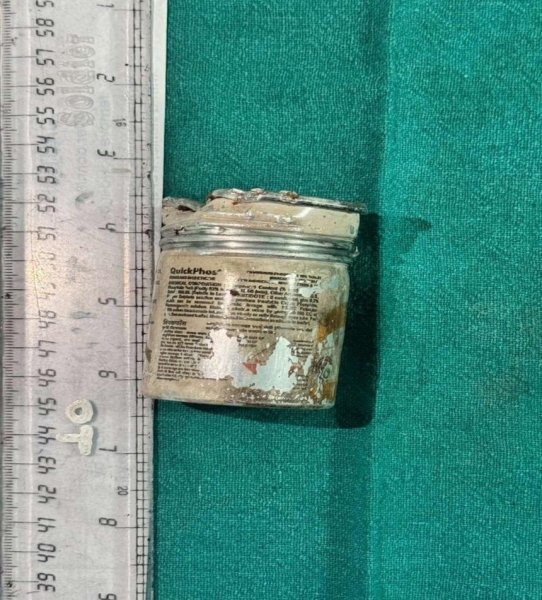

Чоловік, який запхав собі до ануса банку з інсектицидом, залишив її в прямій кишці на шість тижнів. Це сталося після того, як іншому чоловікові засунули в задній прохід 20-сантиметрову секс-іграшку.

Пацієнт поквапився до лікарні, де йому сказали, що у нього розвинувся сепсис на пізній стадії. Медики також зазначили, що його психічний стан “задовільний”. Вони призначили внутрішньовенні крапельниці та антибіотики, і банку було успішно видалено без необхідності хірургічного втручання.

Фермер повністю відновився від впливу інсектицидної банки протягом семи днів. Повідомляється, що він “почувається добре” і отримує консультації та терапію.